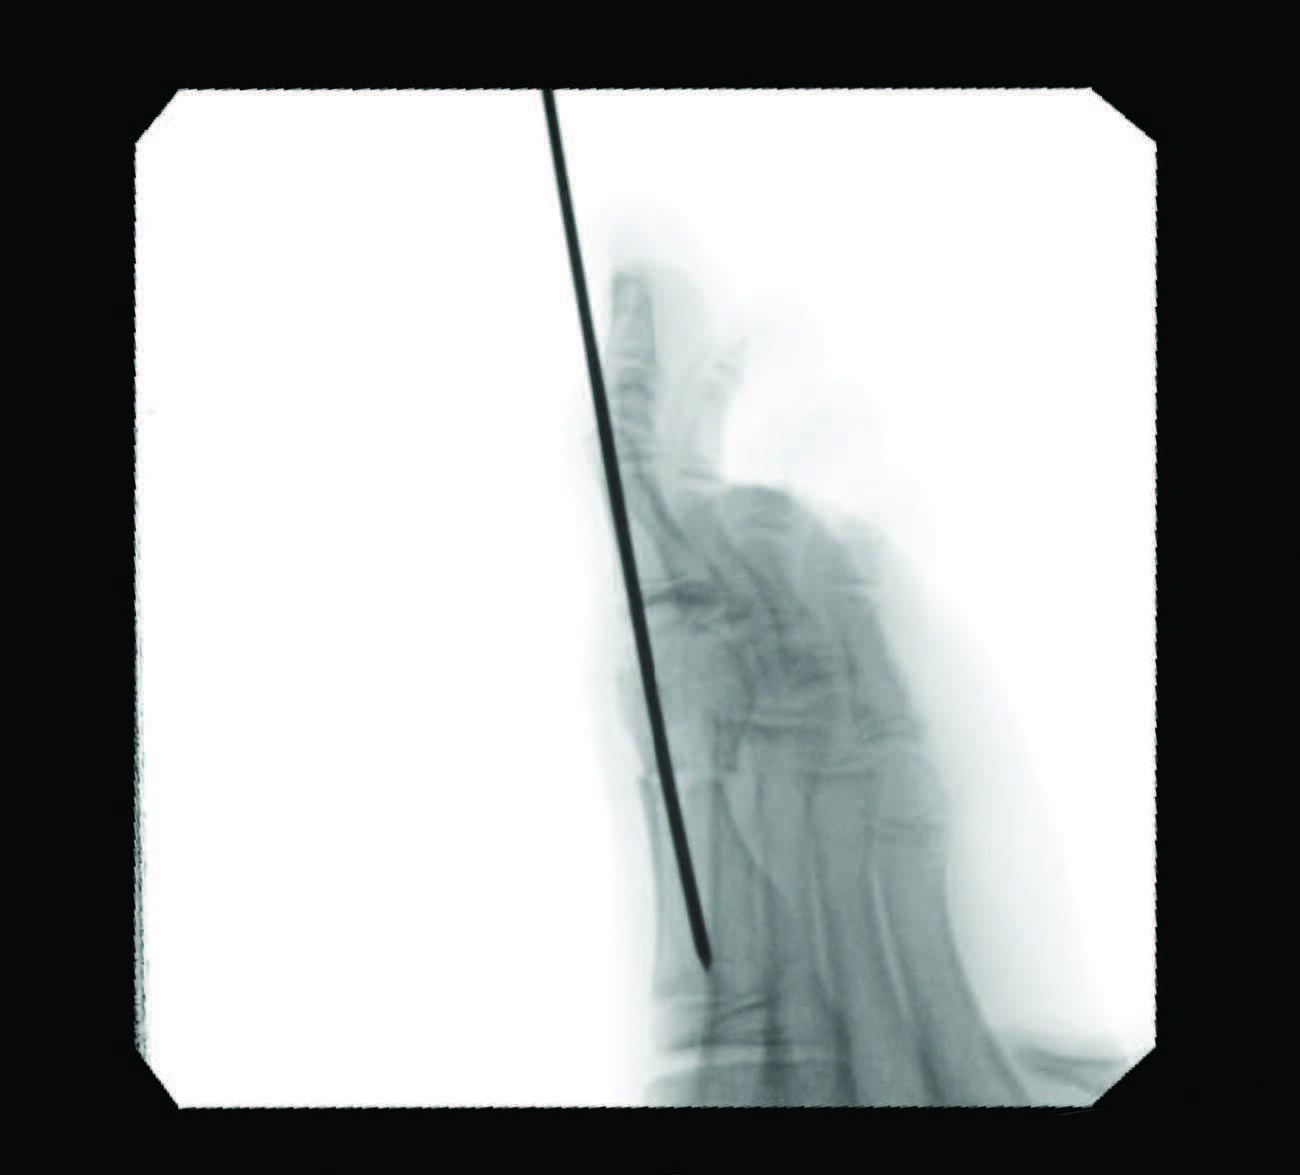

A myriad of open and minimally invasive (MIS) surgical procedures exist for this patient population, with various long-term data demonstrating outcomes, complications, and failure rates. While the literature skeptically portrays early percutaneous procedures, in my experience modern developments in technology have led to much-improved outcomes and techniques, albeit with a lack of long-term data to explain why surgeons continue to shy away from such methods. Minimizing failure rates and increasing patient satisfaction of hallux valgus correction is an important objective of surgeons continuing to improve on traditional methods. The ability of MIS to allow early mobilization by utilizing the same AO principles of traditional methods and the ease of reproducible triplanar correction continues to be a motivation, in my observation, to advance this newer approach and increase its utilization in the podiatric surgical field.

Documentation of surgical correction of hallux valgus first occurred in the early 1800s, with the earliest reports of percutaneous correction in the 1940s. Podiatric physicians experienced surgical restrictions at this time, and MIS provided an avenue for circumvention. Complications arose due to a lack of supportive means, and these outcomes led to an abrupt return to open procedures. The 1960s provided power equipment development and intraoperative fluoroscopy, which significantly improved outcomes of both open and percutaneous procedures. With the arrival of these modern tools, surgeons began to revisit the utilization of percutaneous procedures towards the end of the millennia. A subcapital osteotomy technique reported by Bosch, and “Simple, Effective, Rapid, Inexpensive,” modified by Giannini in the early 2000s, implemented a modern look at MIS hallux valgus procedures.8,9 Most recently, a guide to the percutaneous bunionectomy written by Siddiqui in 2014, and MIS radiographic outcomes in 2016, provided another available tool to surgeons, which decreased the complication rates and expanded the confidence in utilization of MIS bunion correction universally.10

Open and percutaneous osseous procedures rely on physiologic principles of soft tissue and bone healing, where Davis’ and Wolff ’s laws each describe that tissue healing models along imposed demands, according to how they are mechanically stressed. In our experience, allowing patients to weight-bear immediately after surgery will encourage mechanotransduction through stress and load along the osteotomy site. The opposite will occur with a decrease in load and demand along the medial aspect of the first metatarsal, known as the “medial step,” which is just proximal to the osteotomy. Due to the lack of stimulus along the anatomic area, the bone will be less dense; therefore, in theory, it should remodel along the osteotomy site. We feel that one should still consider smoothing out the ‘medial step off ’ along the MIS osteotomy if a ledge is appreciable intraoperatively.

Although minimally invasive hallux valgus surgery is a more modern technique, especially for the pediatric population, it still relies, in my experience, on AO principles of fracture fixation, including anatomic reduction in the first intermetatarsal and hallux abductus angles, stable fixation, preservation of blood supply, and early active mobilization. I find the percutaneous approach allows the reduction of a wide range of mild to severe radiographic angles and preservation of blood supply. In a study of minimally invasive bunion procedures, surgeons achieved up to a 12.5 degree correction of the first intermetatarsal angle and reported a 5.3 percent reoperation rate. The study was from a surgeon’s first 94 MICA procedures, and the author challenged the previously reported steep learning curve, citing low complication rates and ease of reproducibility.13

One can allow early mobilization by immediate weight-bearing in the postoperative course, most notably providing a decrease in adhesions and consequent stiffness of the joint. Another advantage includes multiple viable fixation options, including splintage with a Steinmann pin through external fixation. Many long-term risks of internal fixation include foreign body reaction, growth disturbance, chronic infection, corrosion, implant migration, and potential interference in orthopedic treatment later in life.14 Schmittenbecher and coworkers described risks of implant removal in children with various fixation options, concluding that each patient’s treatment selection must weigh the benefits and risks.14 Steinmann pin fixation may, in my experience, alleviate these risks, removing it around four weeks postoperatively.

As we all know, in stage two of fracture healing, the bone will form a fibrocartilaginous callus; this internal callus houses new blood vessels in the newly formed spongy trabeculae. Therefore, at four-week postoperative radiographs, one may not appreciate a bone bridge across the osteotomy site. As long as an intracapsular osteotomy took place through a minimal approach, I find the capital fragment should stay inherently stable. In my experience, the osteotomy site will form a robust bone bridge through mechanotransduction.